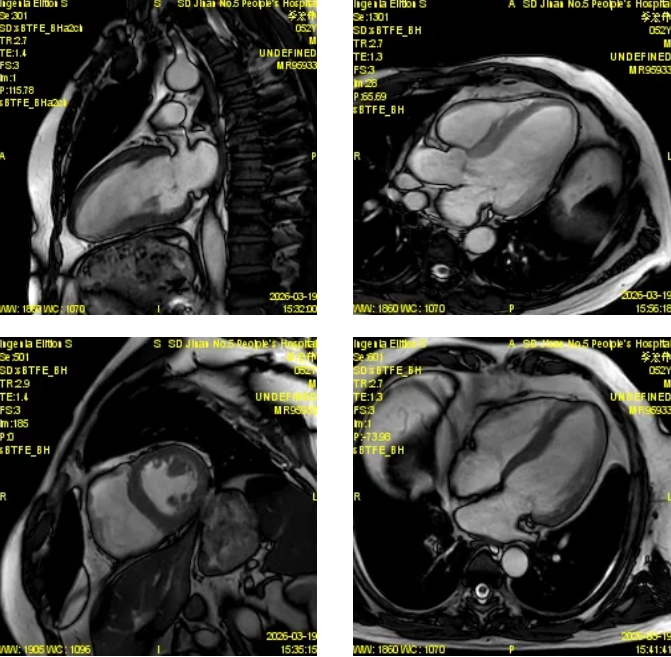

磁共振图像展示

心脏磁共振被誉为评估心脏结构、功能及心肌组织特征的“金标准”,具有无创、无辐射、多参数、精准度高等优势,可以为心肌病、冠心病、瓣膜病、先天性心脏病等疾病提供全面、客观的影像学依据,对临床制定治疗方案、评估预后具有重要意义。